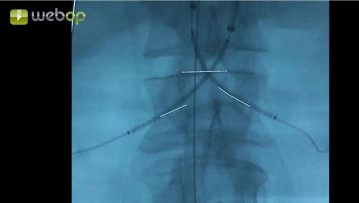

Zugänge transfemoral beidseits, Sondierung Aorta

Toneinstellungen Im Bereich beider Leisten jeweils 5 cm lange Hautinzision, Präparation und Darstellung der Arteria femoralis communis. Anschlingen der Arterien mittels Vessel Loops. Punktion der Arteria femoralis links mittels Kanüle und Vorschieben eines Terumo®-Drahtes unter Durchleuchtungskontrolle nach zentral. Einbringen einer 7F-Schleuse und Gabe von 2000 IE Heparin. Auswechseln des Terumo®-Drahtes über einen Pigtail-Katheter durch einen rigiden Back-up Meier®-Draht. Gleiches Manöver rechts.